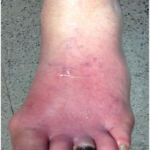

Διαβητική αγγειοπάθεια

Η διαβητική αγγειοπάθεια είναι επιπλοκή του σακχαρώδη διαβήτη που προκαλεί βλάβες στα αιμοφόρα αγγεία, επηρεάζοντας τη σωστή κυκλοφορία του αίματος και αυξάνοντας τον κίνδυνο ισχαιμίας και ελκών, ιδιαίτερα στα κάτω άκρα.